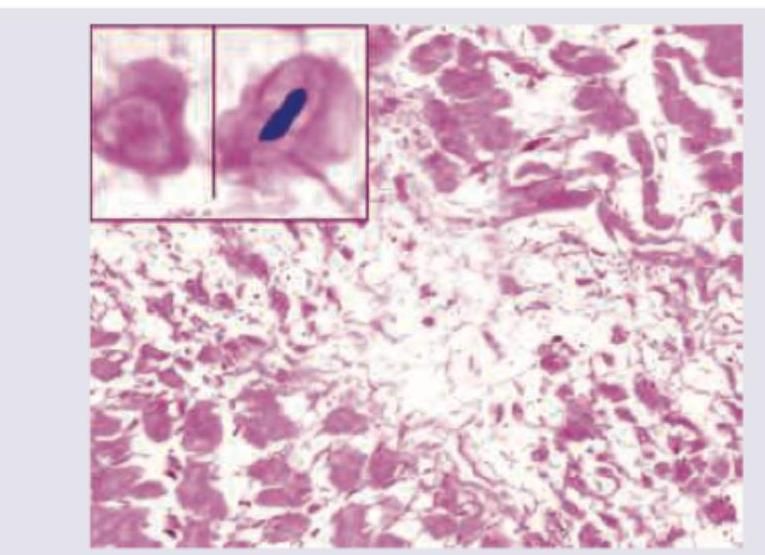

The following image shows presence of:

Explanation: ***Anitschkow cell*** - Anitschkow cells are characteristic **caterpillar cells** or **owl-eye cells** seen in the **Aschoff bodies** of **rheumatic fever** [1]. - They are **enlarged macrophages** with a central, wavy, chromatin-rich nucleus [1]. *Aschoff cell* - Aschoff cells are a type of **modified macrophage** or **Anitschkow cell** that are part of the **Aschoff body**, not a distinct cell type on their own [1]. - The term "Aschoff cell" is often used interchangeably with Anitschkow cell, but Anitschkow cell refers to the specific morphology. *Kulchitsky cell* - Kulchitsky cells are **neuroendocrine cells** found in the **gastrointestinal tract** and **bronchi**. - They are associated with **carcinoid tumors** and produce various hormones. *Langhan cell* - Langhan cells are a type of **multinucleated giant cell** formed from fused **epithelioid macrophages**. - They are characteristic of **granulomatous inflammation**, particularly seen in **tuberculosis**. **References:** [1] Kumar V, Abbas AK, et al.. Robbins and Cotran Pathologic Basis of Disease. 9th ed. The Heart, p. 566.